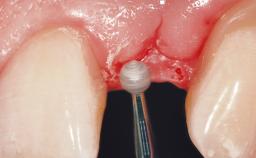

Placement Protocol Immediate implant placement

Tooth Site Maxillary incisor or canine

Socket Morphology Single-root socket

Socket Integrity Damage to one or more bone walls

Bone Volume Damage to one or more socket walls